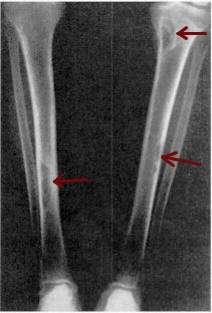

| Osteitis fibrosa cystica of the tibia. Arrows point to the brown tumors which are typically present in bones of people with OFC. | |

X-rays may also be used to diagnose the disease. Usually, these X-rays will show extremely thin bones, which are often bowed or fractured. However, such symptoms are also associated with other bone diseases, such as osteopenia or osteoporosis.[27] Generally, the first bones to show symptoms via X-ray are the fingers.[20] Furthermore, brown tumors, especially when manifested on facial bones, can be misdiagnosed as cancerous.[27] Radiographs distinctly show bone resorption and X-rays of the skull may depict an image often described as "ground glass" or "salt and pepper".[28][29] Dental X-rays may also be abnormal.[3]

Generally, the first bones to be affected are the fingers, facial bones, ribs, and pelvis.[20][21] Long bones, which are longer than they are wide, are also among the first affected.[21] As the disease progresses, any bone may be affected.[16]